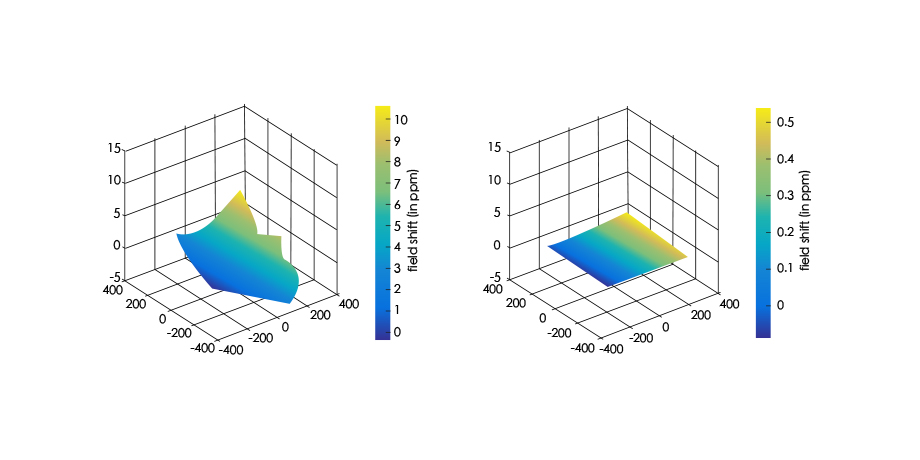

亚秒级

快速智能匀场技术

能在1秒内完成对任意部位,任意区域的快速精准匀场。磁场均匀度可达0.002ppm。在极速匀场过程中,几乎不受运动伪影的影响。

动态B0

涡流补偿技术

改善脂肪抑制效果,减小DWI图像伪影。改善SWI等对B0涡流敏感序列的图像质量